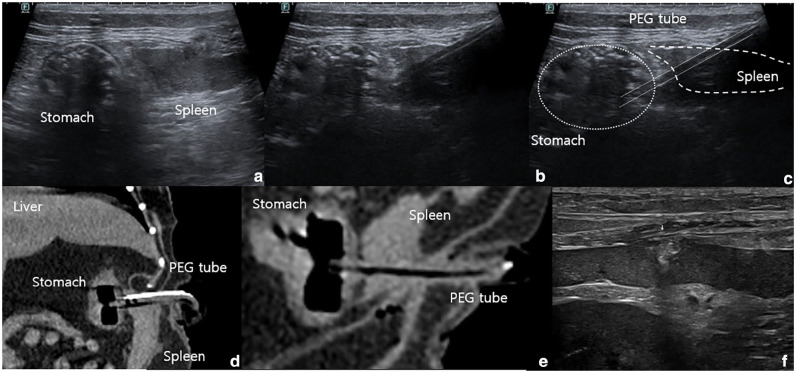

Case summary: A 12-year-old spayed female domestic shorthair cat with a weight of 4.5 kg and a body condition score of 3/9 presented with anorexia and vomiting. Feline hepatic lipidosis was diagnosed based on blood tests and ultrasound examination. Naso-oesophageal tube feeding was initiated, but hypersalivation persisted despite supportive care. As a result of poor feeding tolerance, a percutaneous endoscopic gastrostomy (PEG) tube was placed for long-term enteral nutrition, with endoscopic confirmation of gastric placement. Two hours after the procedure, blood staining on the PEG tube bandage suggested bleeding at the insertion site. Abdominal ultrasonography and CT revealed splenic perforation. A laparoscopic partial splenectomy was performed successfully and the cat recovered without complications. Follow-up laboratory tests demonstrated a gradual improvement in haematological parameters, including haematocrit and total bilirubin. The cat remained clinically stable without further complications.

Relevance and novel information: This report details the first documented case of splenic perforation during PEG tube placement in a cat, successfully managed through laparoscopic partial splenectomy. Minimally invasive laparoscopy has demonstrated efficacy in addressing rare complications, including splenic perforation associated with PEG tube placement in cats.